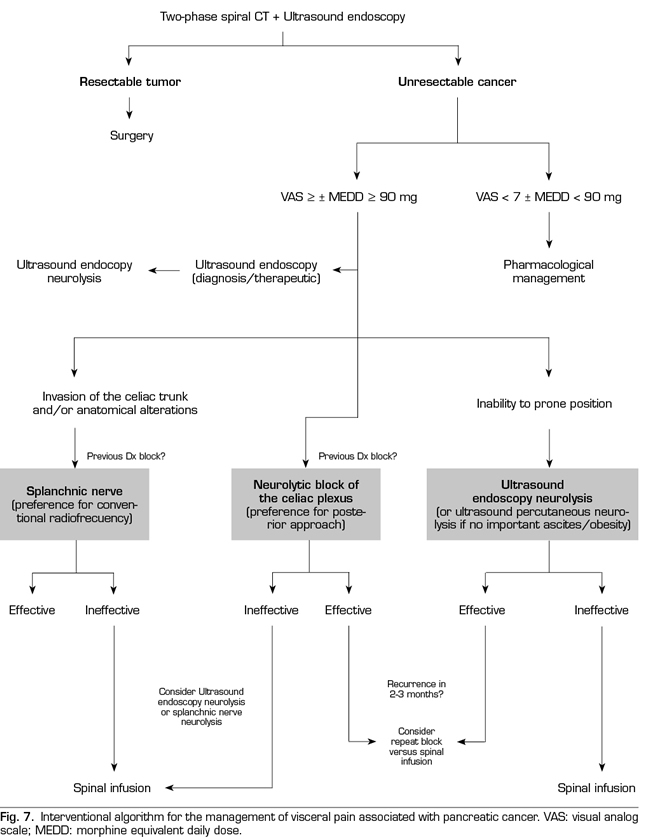

Following the conclusions of the previously described publications, an interventional treatment algorithm for patients with visceral pain associated with pancreatic cancer can be established (Figure 7). The standard procedure would be the posterior approach of the celiac plexus (classical approach), since today it continues being the one with the greatest scientific evidence, preferably transcrural and guided by fluoroscopy, due to its simplicity and speed. Ultrasound endoscopy would be indicated for neurolysis taking advantage of its diagnostic or therapeutic indication, for situations of inability to prone position, and as an alternative in case the posterior approach fails. Percutaneous ultrasound neurolysis would be reserved for selected cases, depending on the experience of the operator, since it is the technique that has fewer publications to date. We hope that in the future, studies allowing ultrasound-guided techniques, whether percutaneous or endoscopic ultrasound, will be published as the “reference method”, since they allow the visualization of surrounding structures with real-time injection control. An alternative to the blockage of the celiac plexus is the conventional radiofrequency of the splanchnic nerves, indicated when there is tumor infiltration of the celiac trunk, important anatomical alterations or if the celiac plexus neurolysis fails. It is also possible to consider a combined neurolysis - neurolytic blockade of the celiac plexus associated with neurolytic block or radiofrequency of the splanchnic nerves -, as reflected in the study of Marra et al. (60), and as we have been performing in our usual clinical practice at HM hospitals, with the aim of increasing the success rate and duration of analgesia without increasing the incidence of complications. However, no enough comparative studies supporting this hypothesis are available so far (Figure 8).

Regarding the ideal time to perform the blockade, our team advocates a neurolysis that is not late despite the fact that the duration of the effect is limited, since we find a series of advantages in patients, such as larger pain management, an improvement in the quality of life, and a lower tolerance to opioids. As indicated by one of the main variables to perform the neurolysis, it is mandatory that the pain is severe, which according to the WHO is estimated at a VAS > 7. Patients with pancreatic cancer and severe pain who undergo neurolysis procedures should be previously treated with potent opioids, being able to establish a morphine equivalent daily dose (MEDD) above 90 mg to confirm the blockage decision, or below if the patient present significant side effects derived from opioids.